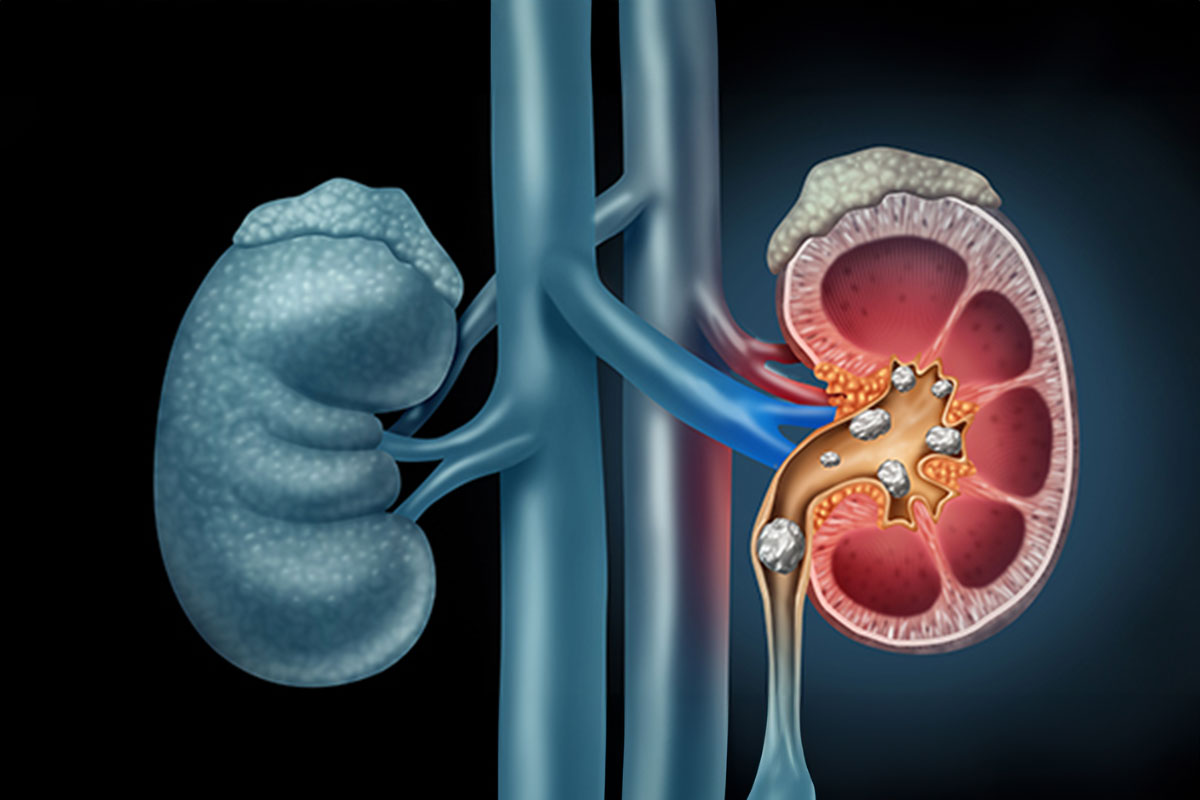

Urinary stones

Occurs due to drinking heavy water, increased oxalate contents in diet, builging of increases uric acid in blood due to metabolic problem, habit of drinking less water etc. It can be passes through urinary tract after breaking/melting well on its merits with help of hollistic homeopathic remedies selected after proper case taking, which can provide lasting cure, along with dietery changes.